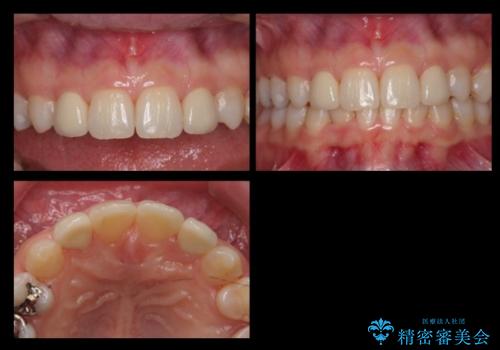

前歯を整えたい 小さい前歯がある 矯正・セラミック併用で美しく インビザラインでも抜歯矯正できます

- 前歯を整えたいと来院。

左右の前から2番目の歯が細く、矮小でした。

また、奥歯が2つ並んでおり歯ブラシがしにくい状態でした。

内側に入っている左上5を抜歯しています。

抜歯したスペースを使い、歯並びを整え、さらにその隙間を利用して細い歯を大きく整えてセラミックで被せるという総合的な治療を行いました。

マウスピース矯正→上顎両側2番のセラミック、左下67の虫歯治療 の順で行いました。